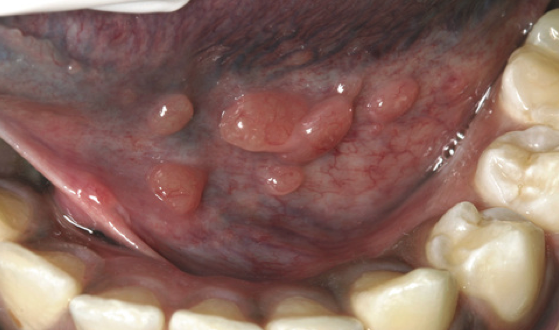

What is the likely Dx?

Lymphoid hyperplasia.

Leukemia.